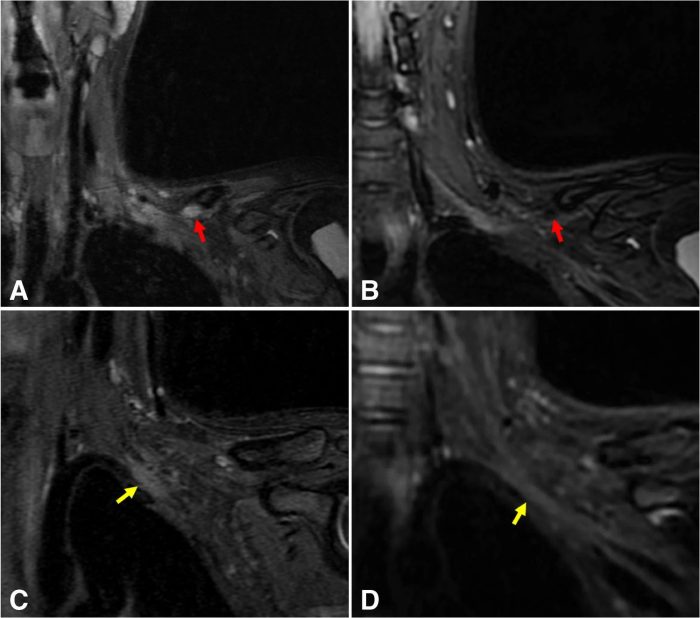

Improved suppression of blood vessel signal on the proposed sequence compared to T2w-FSE-FLEX. A T2w-FSE-FLEX and B MSDE-CUBE-fTED are from one subject, and C T2w-FSE-FLEX and D MSDE-CUBE-fTED are from another subject. For each case, the most comparable slices were chosen to mitigate the slight difference of the imaging axis and slice thickness between the two sequences. The signal from the suprascapular vein in the infraclavicular region (red arrows) is quite strong on the T2w-FSE-FLEX image (A), while it is well suppressed on the image of the MSDE-CUBE-fTED sequence (B, red arrow). On the T2w-FSE-FLEX image (C), adjacent subclavian vessel walls are often difficult to separate from the brachial plexus structures (yellow arrow), whereas on the image of the MSDE-CUBE-fTED sequence (D, yellow arrow), this does not pose a problem due to the robust vessel signal suppression and thinner slice thickness, reducing partial volume effects